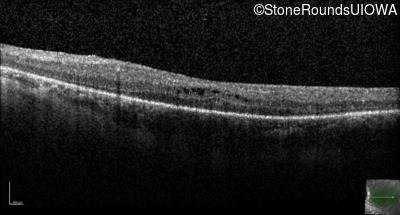

Optical Coherence Tomography - Right - 20/80 sc

Exemplar / OCT Stack